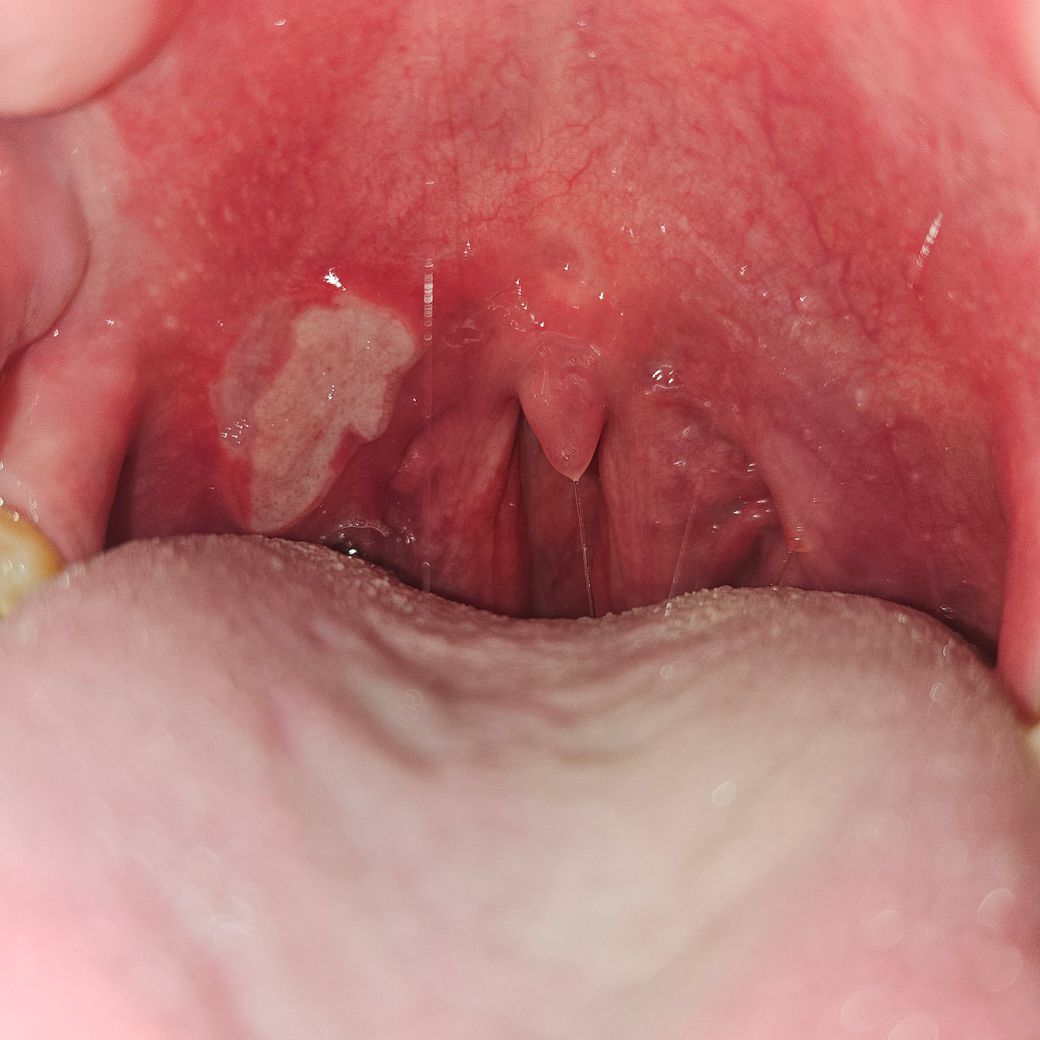

같은자리에 구내염이 생기는데요 무섭습니다...

구내염이 크게났다가 다나은자리에 구내염이다시 생겼습니다 현재는 다나아가는중인데 같은자리 구내염이 생긴다면 문제가있는걸까요?

큰구내염이 생기고 아문후 흉터같은것도 생겼습니다..

첫번째 약 9월경 사진

두번째 약 10윌경 사진

세번째 일주일전 사진

네번째 어제사진 입니다.

짧은 주기로 구내염이 반복되거나 포도막염, 생식기 궤양이 동반되는 경우 자가면역성 질환의 가능성에 대해 류마티스 내과 진료를 받아볼 것을 권합니다.

과도한 스트레스, 불균형한 영양의 섭취, 음주, 흡연, 자극적 음식의 섭취도 구내염의 원인이 되므로 주의하기 바랍니다.